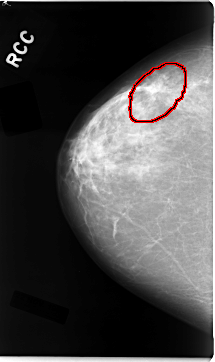

C_0034_1.RIGHT_CC

RIGHT_CC LINES 4704 PIXELS_PER_LINE 2784 BITS_PER_PIXEL 12 RESOLUTION 50 OVERLAY

FILE: C_0034_1.RIGHT_CC.OVERLAY

TOTAL_ABNORMALITIES 1

ABNORMALITY 1

LESION_TYPE MASS SHAPE IRREGULAR MARGINS SPICULATED

ASSESSMENT 5

SUBTLETY 5

PATHOLOGY MALIGNANT

TOTAL_OUTLINES 1

BOUNDARY